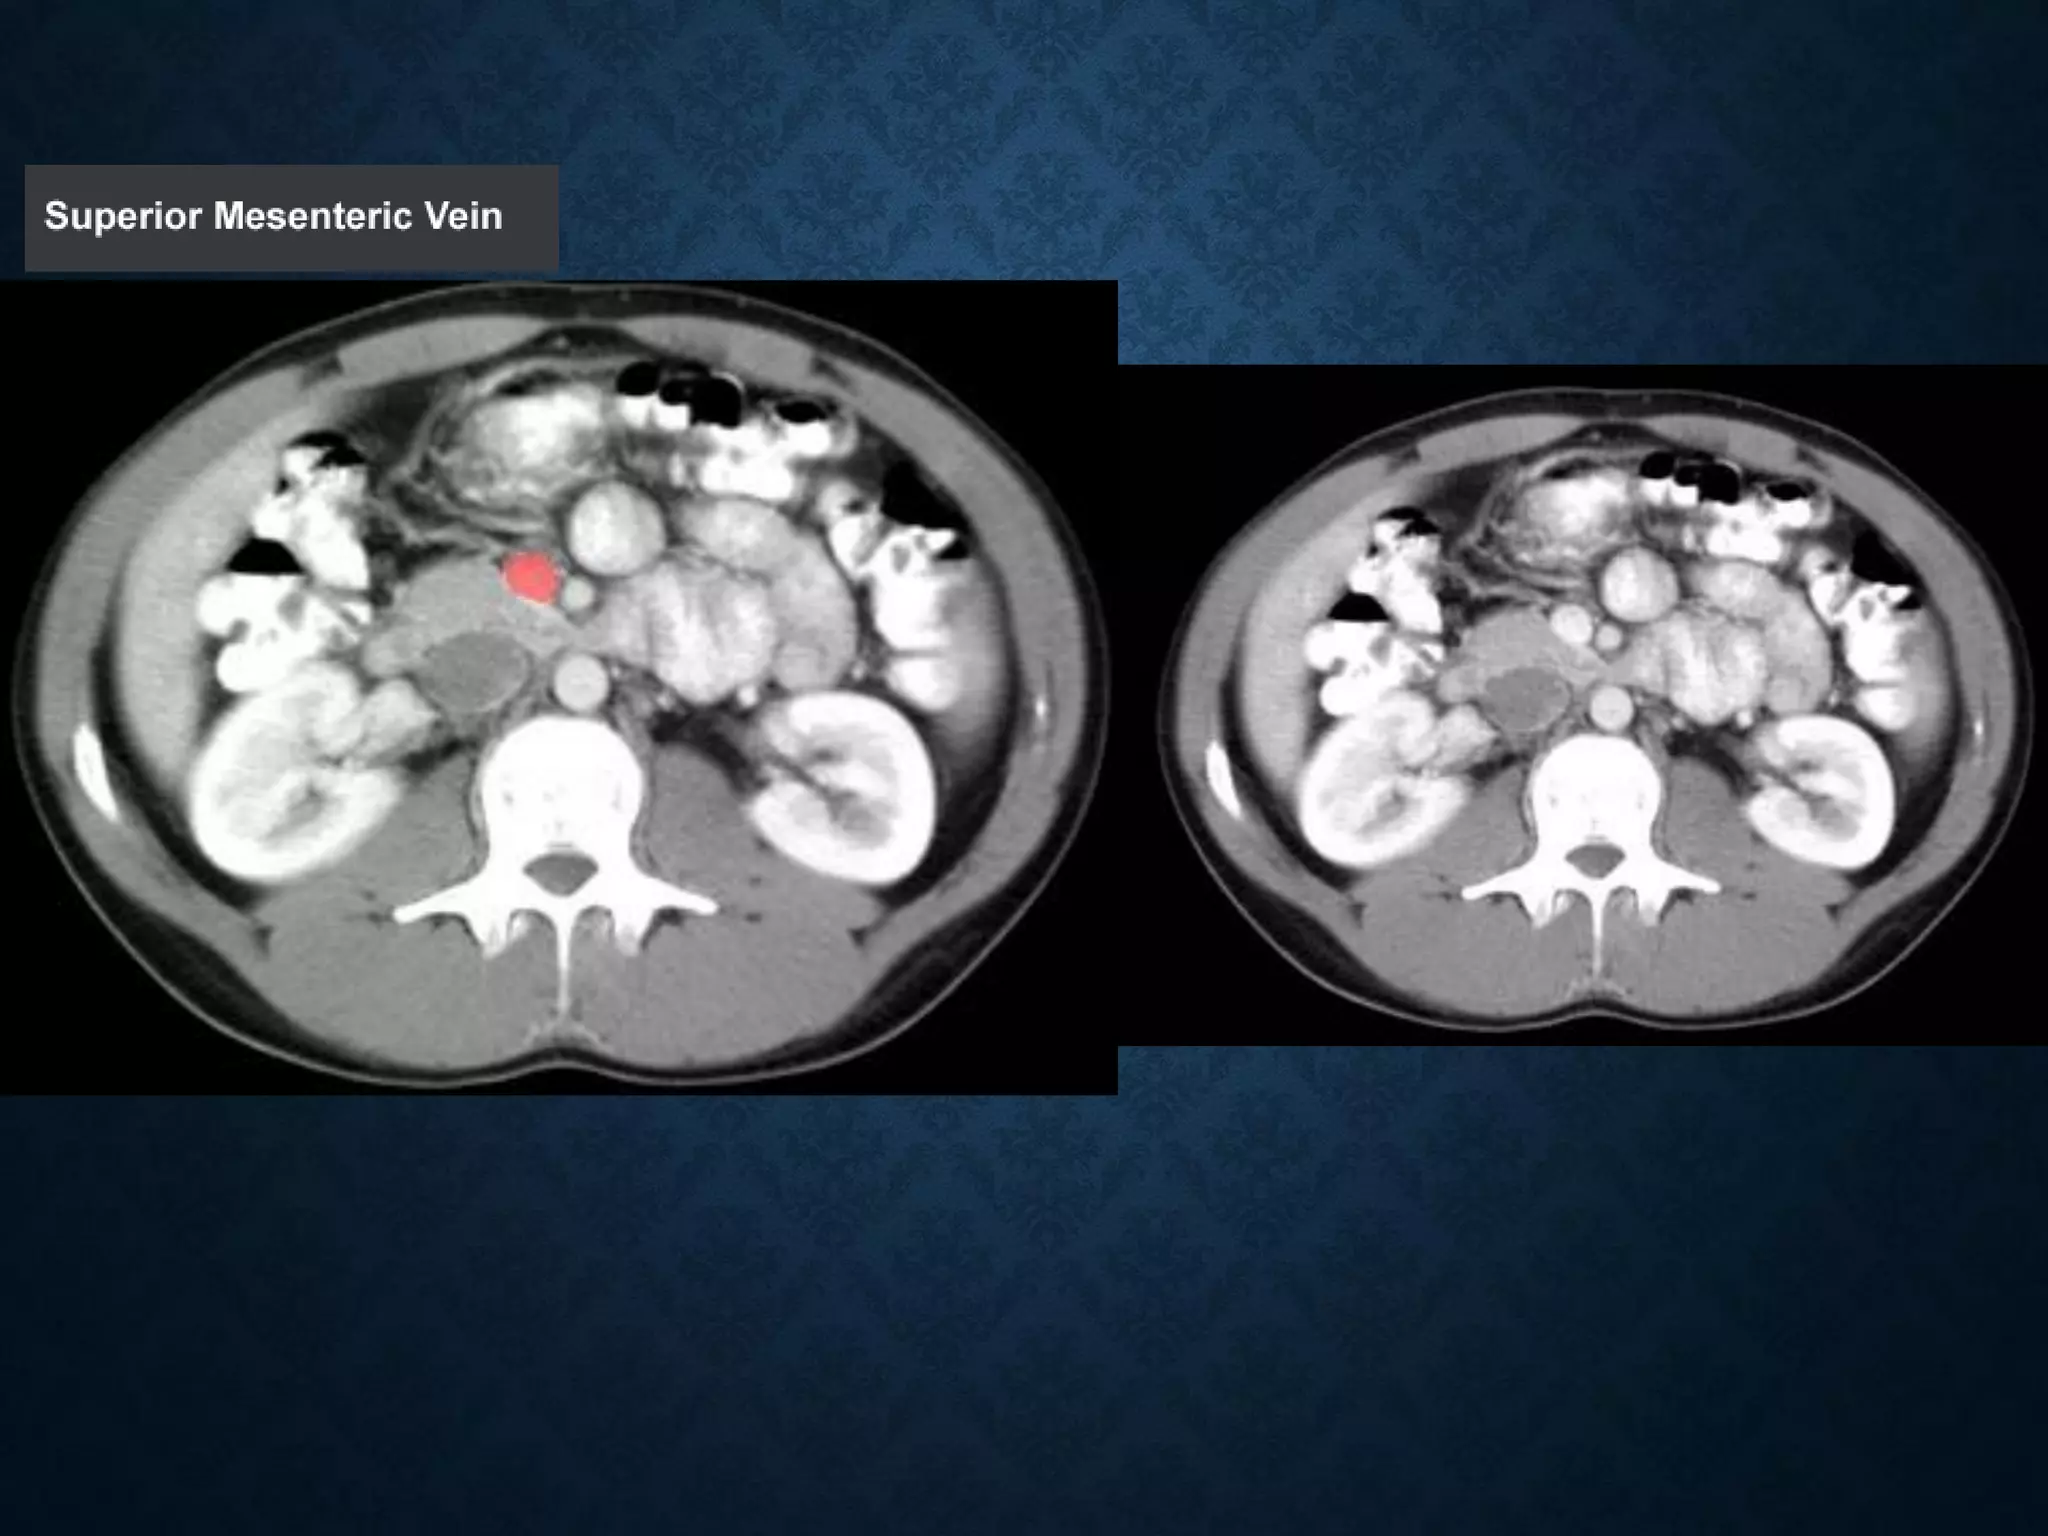

SUPERIOR MESENTERIC VEIN

• In anatomy, the superior mesenteric vein (SMV) is a blood vessel

that drains blood from the small intestine (jejunum and ileum).

• At its termination behind the neck of the pancreas,

• the SMV combines with the splenic vein to form the hepatic portal vein.

• The SMV lies to the right of the similarly named artery, the superior

mesenteric artery, which originates from the abdominal aorta.

SUPERIOR MESENTERIC VEIN •In anatomy, the superior mesenteric vein (SMV) is a blood vessel that drains blood from the small intestine (jejunum and ileum). • At its termination behind the neck of the pancreas, • the SMV combines with the splenic vein to form the hepatic portal vein. • The SMV lies to the right of the similarly named artery, the superior mesenteric artery, which originates from the abdominal aorta.